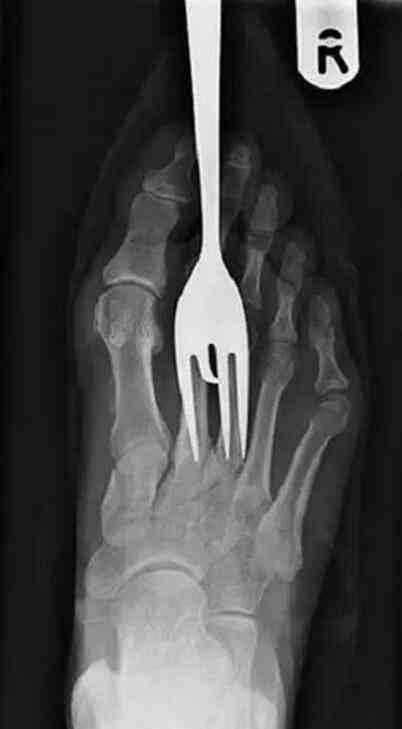

千万别把勺子放在地板上